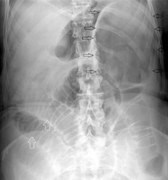

Small bowel obstruction

- Air in colon or rectum makes complete obstruction less likely (esp if symptoms >24hr)

- Abdominal x-ray has poor Sn and Sp for SBO

- If concerned need CT